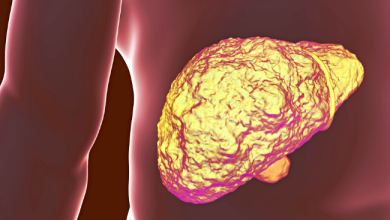

علامات بعضها يظهر على الجلد تشير إلى مرحلة متقدمة من مرض الكبد الدهني

مرض الكبد الدهني غير الكحولي (NAFLD)، هو مجموعة من الحالات التي يسببها تراكم الدهون في الكبد، والتي يمكن أن تتسبب…